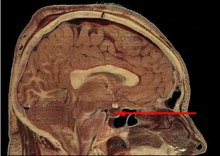

Pituitary gland

The pituitary gland in the skull, relative to the brain and nasal cavity, courtesy Jomegat via Wikipedia

• As can be seen in the scan, the position of the pituitary is directly behind the nasal cavity in the skull as such, Taub is right that it can be reached by going up the nose through the front of the skull.